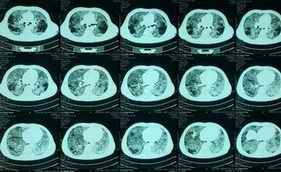

图片1 患者肺部CT:两肺毛玻璃样变